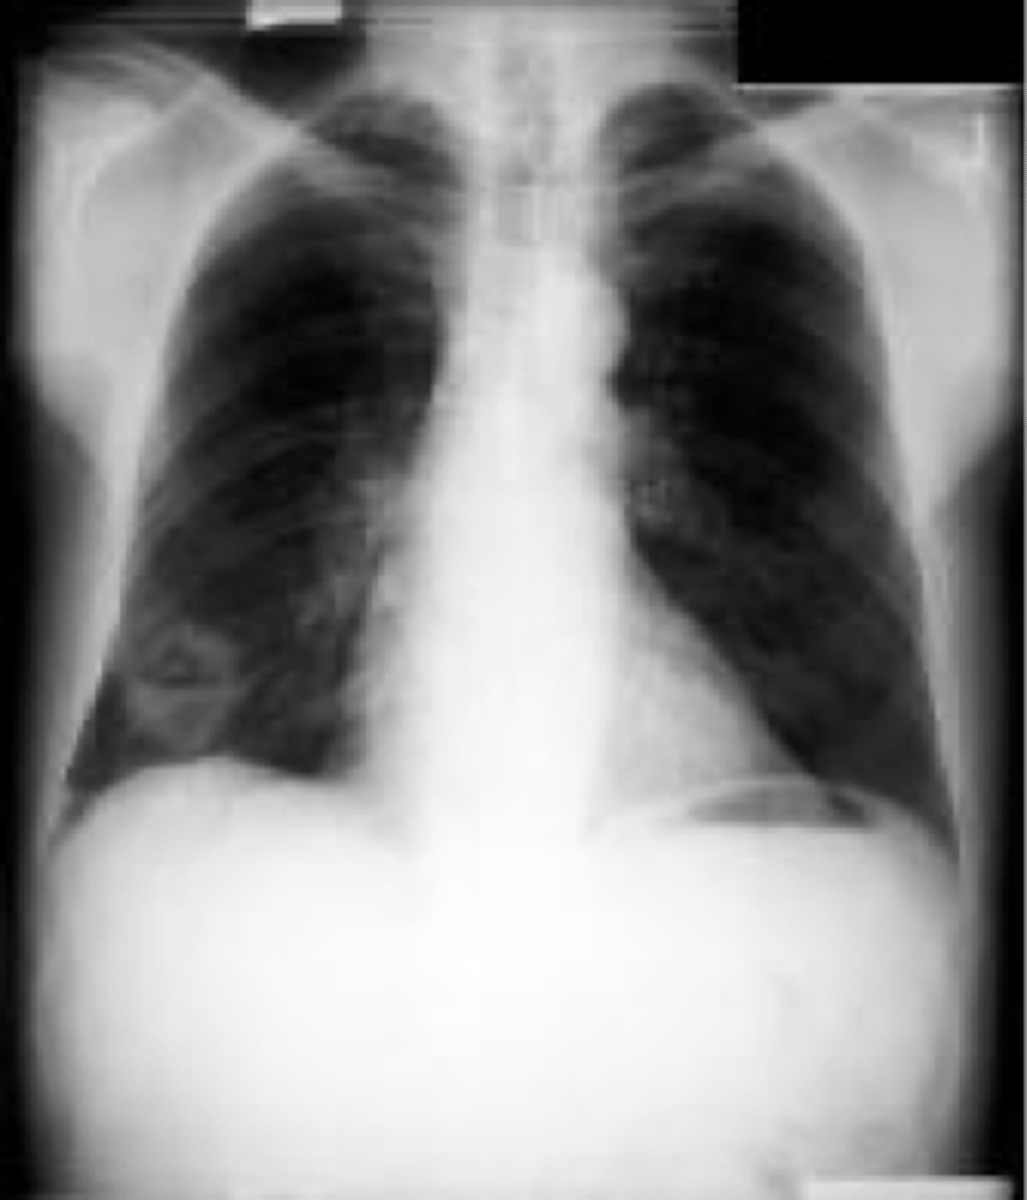

lung abscess

ARDS